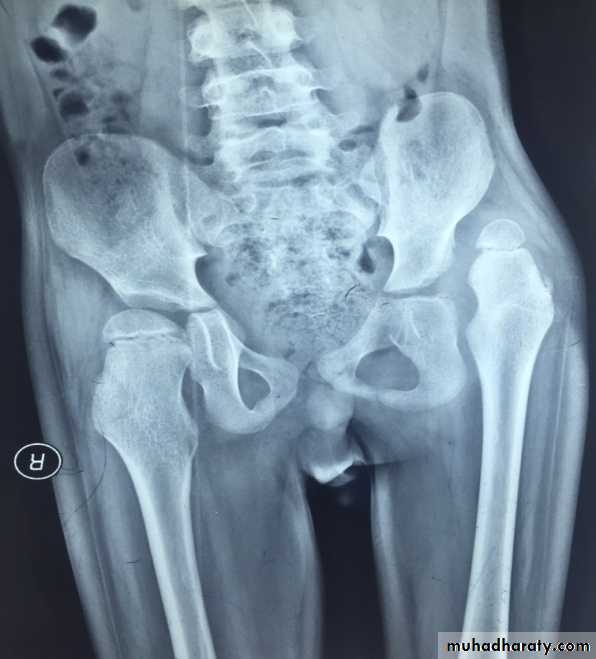

Imaging

1- Ultrasound is used in the 1st 6 months .2- Plain x-ray is used as follow .

A- Von-rosen’s line in the 1st 6 months .

B- Perkin’s line above the age of 6 months

C- shunton’s line above the age of 6 months.